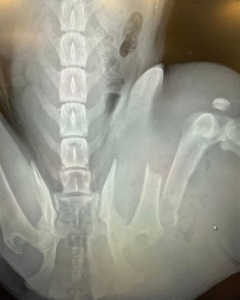

Blue here! I still have a long road to recovery, I have plates keeping my leg together and my foster mom tells me I have to rest for 12 whole weeks! So far, I’m enjoying the resident dog and cats, and I love getting pets and cuddles from all humans, especially children. In a few days I go back to the vet, where they will take my drain out. That will feel so much better! I will also need to have x-rays taken again to make sure my leg bones are healing ok. For now, I will get some much needed rest in my nice warm foster home, and I’m so grateful for all these nice people for giving me a second chance.

Meet Blue: This young female pup was hit by a vehicle and left for days with no treatment. Thankfully, a kind lady called for help. Blue has a badly broken leg with a large abscess and an enlarged kidney, and is currently being treated at Guardian VCA. Blue wants to thank all the kind people who call in about injured dogs that are in desperate of help, the amazing vets and staff who we all depend on for giving them the medical care they need, and of course all the supporters who make it all possible.